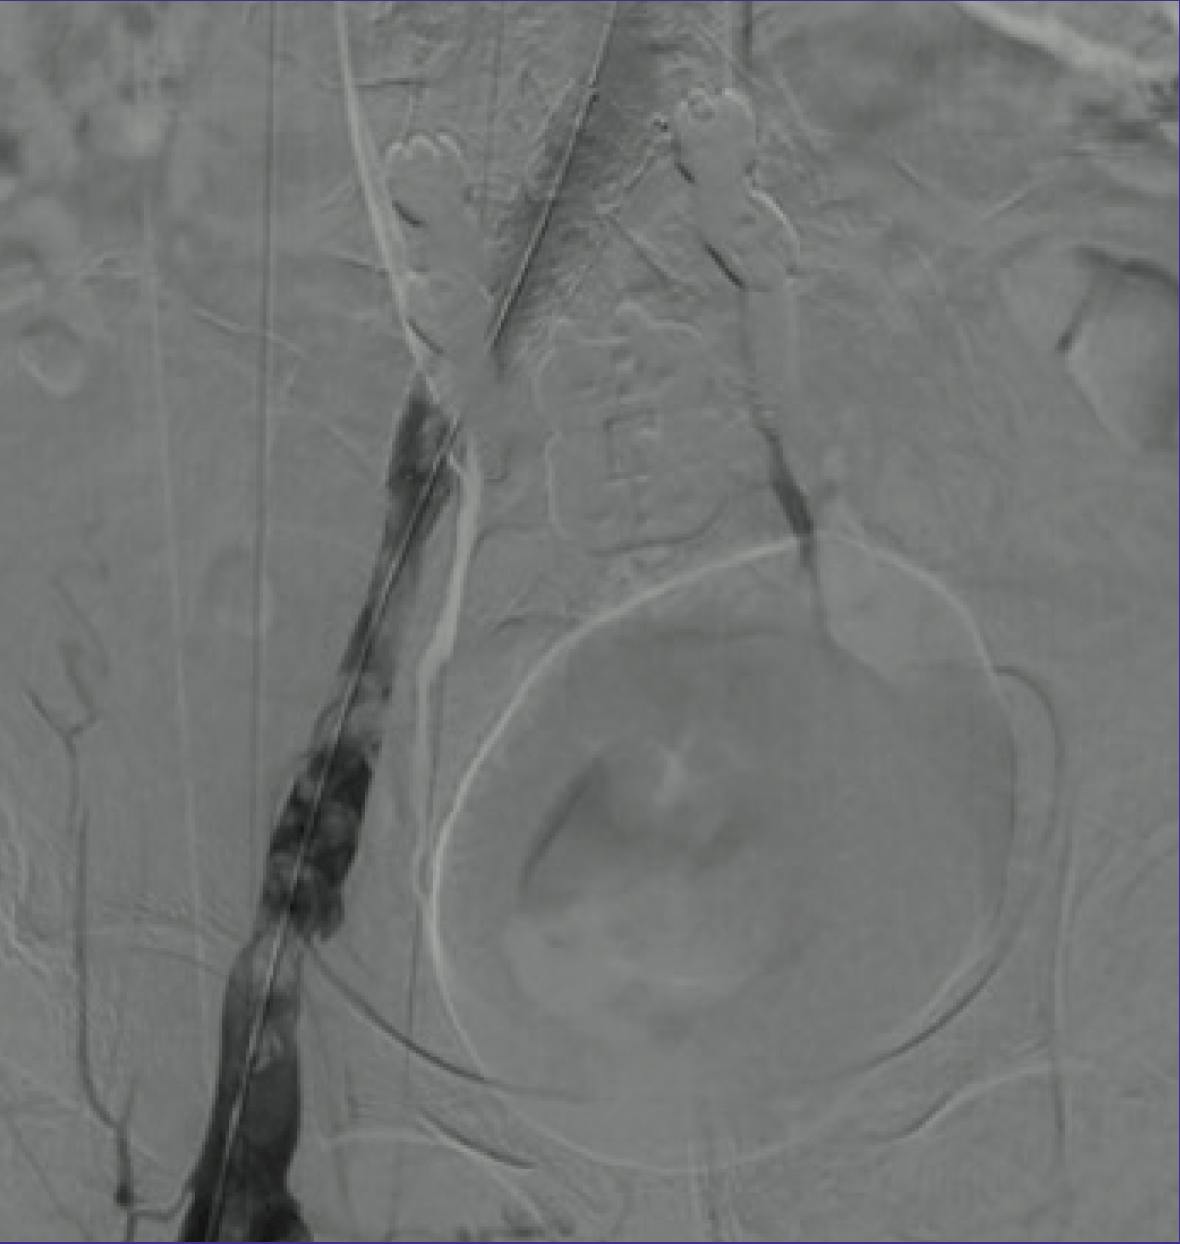

CT scan revealed thrombus extending from the left tibial vessels to the external iliac vein, with May-Thurner narrowing. In the prone position, left popliteal access was obtained, a 12 Fr Pounce™ Sheath (Surmodics, Inc.) was placed, and a .035 guidewire and support catheter were navigated into the inferior vena cava. Venography demonstrated near-occlusive DVT from the accessed popliteal vein to the common iliac vein (CIV), with extensive collateralization (Figure 1).

Figure 1. Initial venogram showing near-occlusive DVT extending from the accessed popliteal (far left) vein to the CIV (far right) and extensive collateralization.